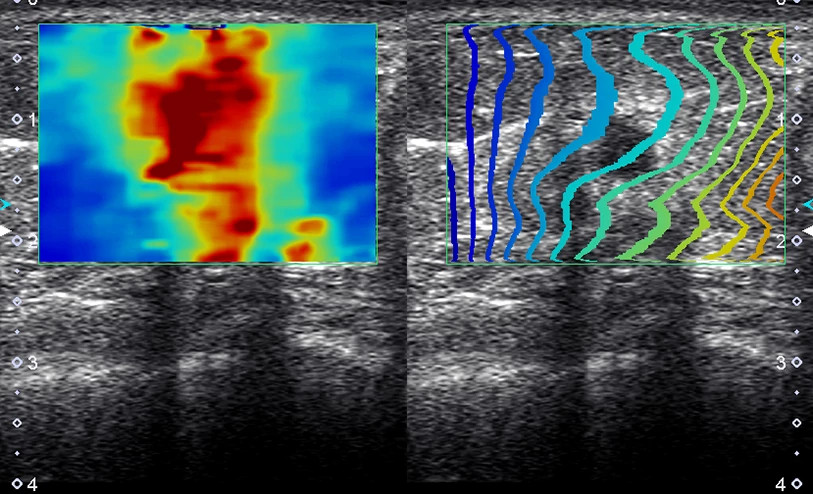

A Canon Shear Wave technológiája kvantitatív és dinamikus vizuális információt nyújt a szöveti merevségről különböző klinikai környezetekben.

Multi-Parametric Report - Integrált jelentés májalkalmazásokhoz

A multiparametrikus jelentés képes egyesíteni az ultrahangos és külső vizsgálatok (pl. laboreredmények) adatait, hogy átfogóbb képet adjon a máj állapotáról.

Az eredmények táblázatos formában vagy pókháló (spider) diagramon is megjeleníthetők, ahol a vizuális mintázat segíti az eredmények közötti összefüggések értelmezését.

A jelentés kombinálható a következő modulok eredményeivel:

Shear Wave Elastography

Shear Wave Dispersion Map

Attenuation Imaging